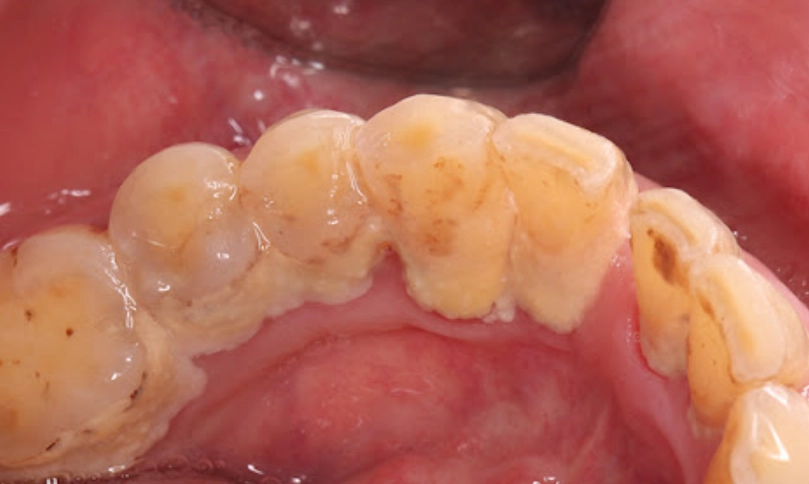

牙結石就是牙菌斑鈣化後的硬塊,通常堆積在牙齒和牙齦交界處,光靠刷牙很難清掉。洗牙機,也叫水牙線,用高壓水流沖洗這些死角。我自己發現,即使每天刷牙,牙縫後方還是會積一點黃色垢,那就是牙結石的前身。

牙結石如果不處理,會慢慢導致牙齦炎甚至牙周病。洗牙機能輔助清潔,但對於已經形成的硬塊,還是得靠牙醫的超音波洗牙。家用洗牙機更適合日常維護,防止新結石生成。